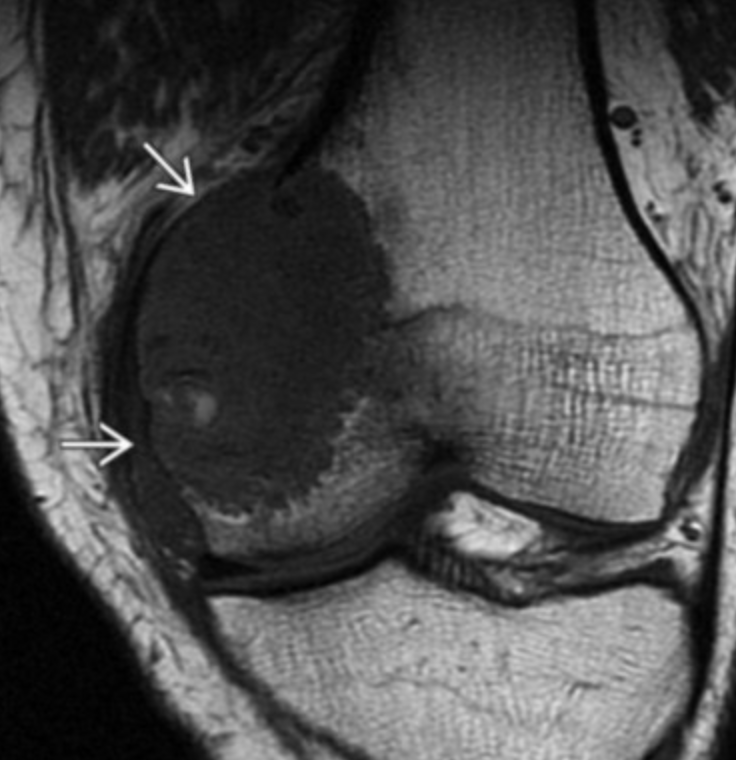

Synovial Sarcoma

• Misnomer as does not actually arise from synovium or in the joint but typically adjacent to joint

• Strong predilection for the extremities

• Relatively young 15-40 yo

• Slow growing and does not have to be painful

• Calcifications about 1/3 of the time

• Not required but commonly located next to a neurovascular bundle (popliteal space, anterior shoulder for example)

• Triple sign

• 3 different densities

• Looks like teratoma in the soft tissue, sometimes, other times just looks like a fucked up mass

• Split fat sign

• Very thin line of fat along periphery of mass, very subtle

• Heterogenous on MR with internal necrosis